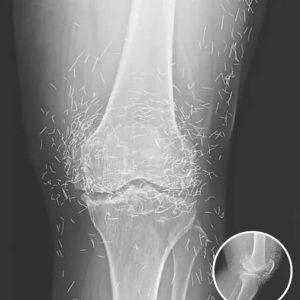

Doctors Shocked by What They Found Inside Woman’s Knee During Routine X-Ray

A 65-year-old woman in South Korea visited the hospital expecting confirmation that her swollen, painful knees were due to arthritis. Instead, X-rays revealed something shocking—her joints were…